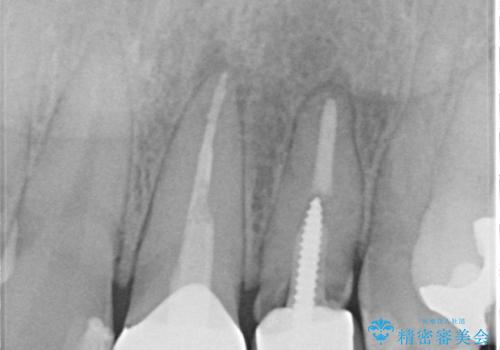

レントゲンを撮影すると、不適合のかぶせ物が装着されており、根管治療も不十分でした。

左上の1番目、2番目の歯を根管治療からの再治療を行う計画としました。

レントゲン上でも適合の良いかぶせ物が装着できています。